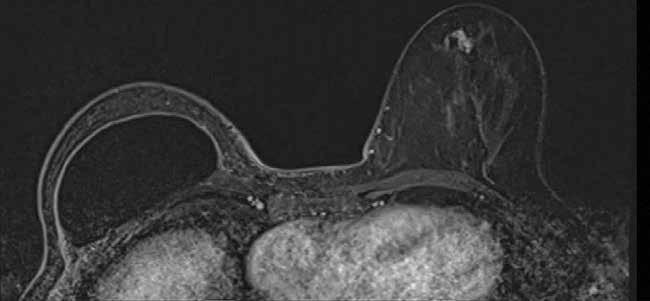

Mujer de 52 años, portadora de mutación BRCA-2, en seguimiento des de febrero de 2005 por un carcinoma ductal infiltrante en mama derecha tratado mediante mastectomía radical, quimioterapia, radioterapia y tra tamiento hormonal posterior. Revisiones periódicas normales hasta mar zo de 2021, detectándose microcalcificaciones de nueva aparición en una mamografía de control de la mama izquierda, que se confirman mediante tomosíntesis y ecografía. En el estudio con resonancia magnética, la lesión corresponde con un realce tipo no masa, sugestivo de malignidad y asocia múltiples adenopatías axilares ipsilaterales. La paciente refiere previa ad ministración de la vacuna COVID-19 en el brazo izquierdo, planteándose el diagnóstico diferencial entre adenopatías post-vacunales vs metástasis ganglionares de un foco invasivo. Se realiza biopsia tanto de la lesión ma maria como de los ganglios axilares, confirmándose histológicamente el diagnóstico de recidiva tumoral contralateral con un carcinoma ductal in situ y linfadenitis reactiva post-vacunal.

Historia de la enfermedad: